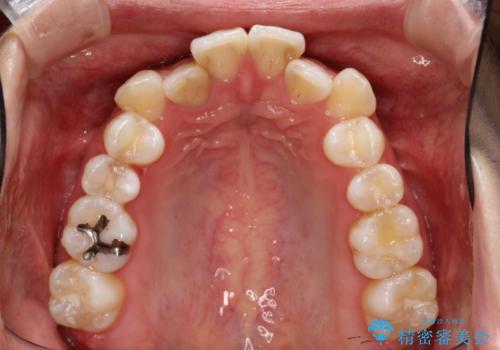

目立たない装置を希望されたので、上顎が裏側装置のハーフリンガルを選択し、上下左右の小臼歯(計4歯)を抜歯して矯正治療を行うこととしました。

治療期間の目安は3年~3年半でしたが、咬み合わせにより上顎のスペースがなかかな閉じきらず、治療期間が長期化してしまいました。

期間はかかったものの、口元の張り出し感や歯のデコボコが解消され、患者様には大変満足していただけました。